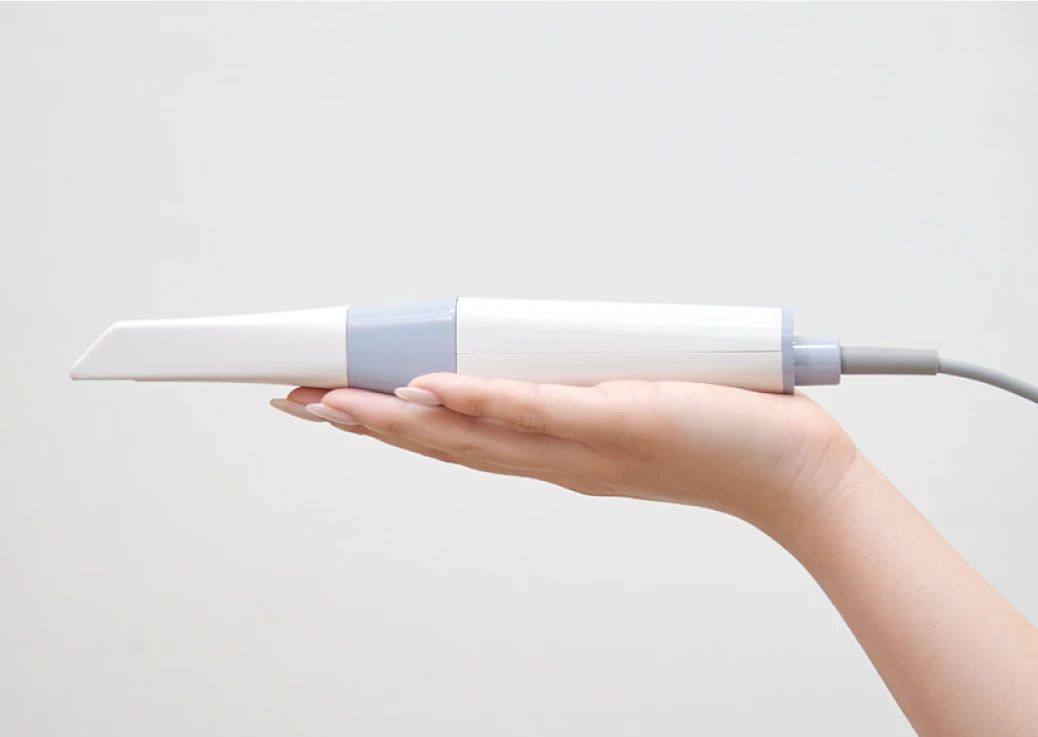

当院ではお口の型取りを「光学スキャナ」を使用して行います。型取りと言うと、息苦しい、辛いといったイメージをお持ちの方もいらっしゃると思います。

しかし、光学スキャナはお口の中をスキャンするだけで、精密な型取りが可能です。嘔吐反射が強い方など、多くの方からご好評をいただいています。